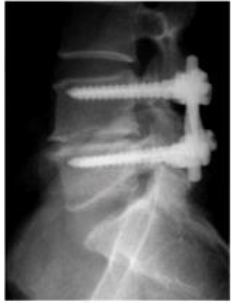

Sobre a imagem abaixo assinale a alternativa correta:

enunciado 1019108-1